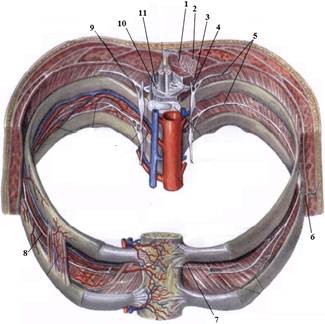

ТЕМА: Грудні нерви, розподіл дорсальних (задніх) гілок. Яремний, підключичний і бронхосередостінний стовбури. Міжреброві нерви, хід, топографія, ділянки іннервації. Судинно-нервовий пучок міжребрового проміжку.

е) склад та топографію судинно-нервового пучка міжребрового проміжку.

7. Судинно-нервовий пучок міжреберного проміжку.

На таблицях і трупах студенти знаходять судинно-нервового пучка міжребрового проміжку. Далі на трупі розглядають хід і розподіл грудних нервів та ділянки їх інервації, Користуючись таблицями вивчають лімфатичні судини і вузли грудної клітки. На трупі ззаду і справа від грудної аорти знаходять грудну протоку. Визначають її корені хід топографію. На таблицях вивчають корені правої лімфатичної протоки визначають ділянки відпливу до двох головних лімфатичних проток.Викладач консультує студентів по темі заняття, показує незрозумілі деталі будови. В кінці заняття викладач шляхом тестування кінцевого рівня знань та вмінь оцінює роботу кожного студента в академічному журналі.

1. Яким номером позначено N. thoracicus?

2. Яким номером позначено N. intercostalis?

3. Яким номером позначено R. cutaneus lateralis?

4. Яким номером позначено R. dorsalis n. thoracici?

5. Яким номером позначено R. cutaneus lateralis r.dorsalis n. thoracici?

6. Яким номером позначено R. cutaneus medialis r.dorsalis n. thoracici?

7. Яким номером позначено R. cutaneus anterior?

8. Яким номером позначено Rr.communicantes n. thoracici?

9. Яким номером позначено Radix dorsalis n. thoracici?

10. Яким номером позначено Radix ventralis n. thoracici?